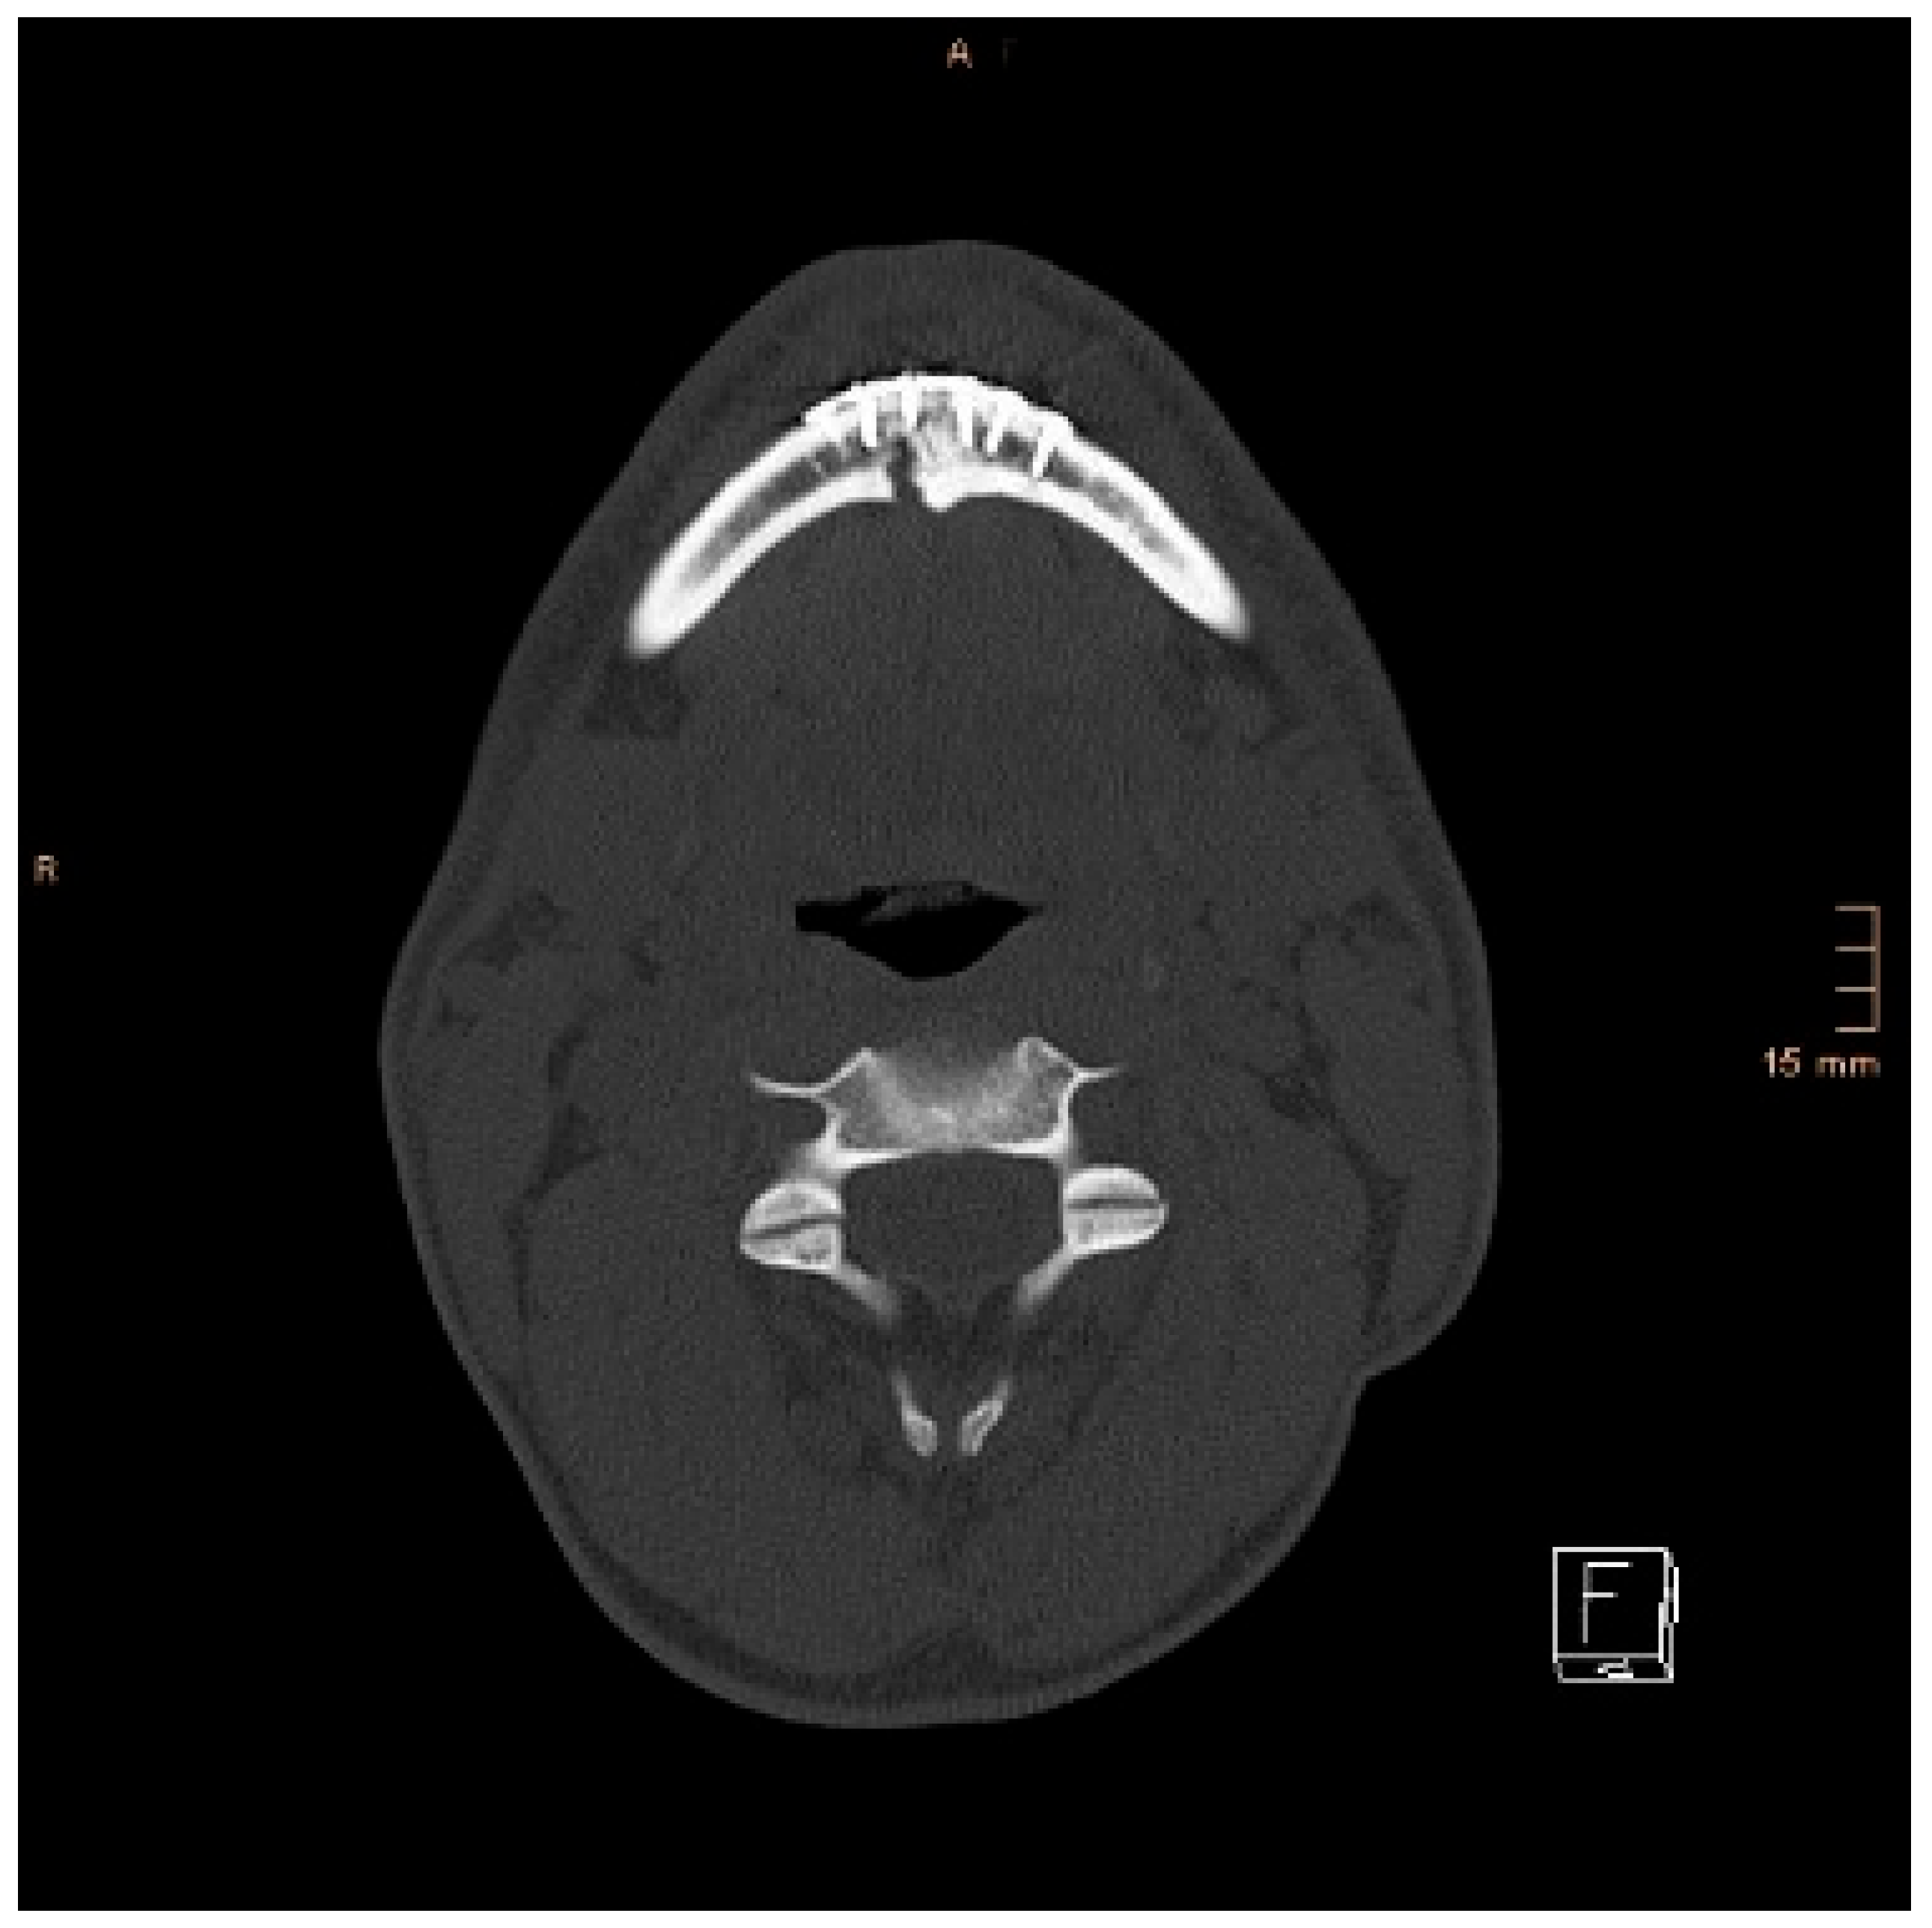

Two operations had to be redone because of inadequate reposition in the symphysis/parasymphysis with broad (>2 mm) lingual splay. In both cases, straight miniplates were removed. Osteosynthesis was achieved with lag screws. Figure 3 depicts plate osteosynthesis of a symphyseal fracture with a broad lingual gap (Figure 3). Figure 4 shows the same patient after redo operation and osteosynthesis of the same fracture with a lag-screw and a marked reduction in the lingual splaying (Figure 4). Figure 5 demonstrates the condylar reduction in the frontal plane in the same patient. Figure 6 and Figure 7 show the patient’s occlusion (Figure 5, Figure 6 and Figure 7). The third redo operation was due to nonunion and infection of an angular fracture with fracture of the two condylar plates. In this case, after removal of the infected miniplate, the angle fracture was stabilized with a reconstruction plate and a miniplate from an extraoral approach; the two broken miniplates at the condylar process were left in situ.

Figure 4. Axial CT scan showing the same patient as in Figure 3 after replacing the miniplates with a lag screw and considerable closure of the lingual gap. However, a small gap in the lingual cortical bone remained, and possibly determined a widening of the mandible.